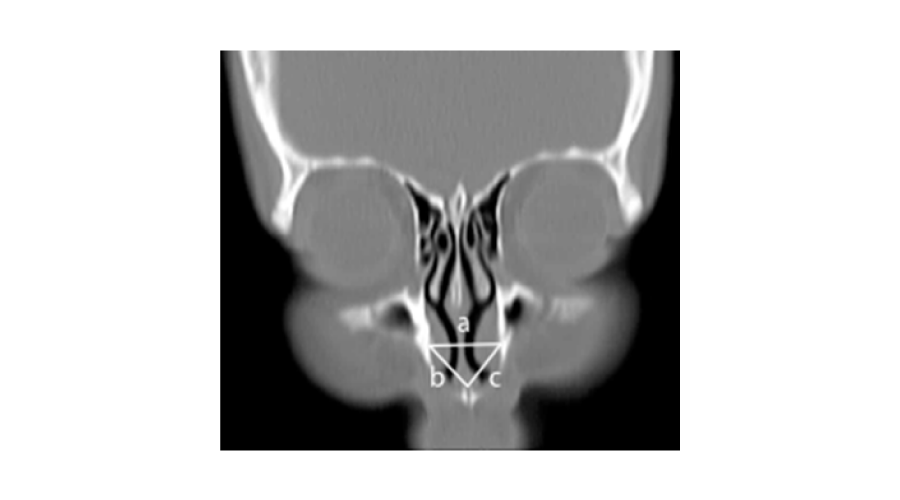

1. The following parameters on the midsagittal images were measured (Figure 2)The height of the pyriform aperture (PAH): the distance between the lowest point of the nasal bone and anterior nasal spine.

Figure 2:

2. The upper anterior face height (UAFH): the distance between nasion and anterior nasal spine.

3. The anteroposterior length of the maxilla (LM): the distance between anterior and posterior nasal spine.